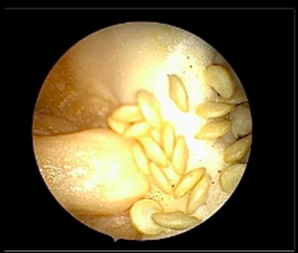

Instruments and Technique: Each training set up had a 2.9mm 30° hysteroscope with a 5mm operative sheath, connected to a camera control unit and monitor, with an LED light source as the primary operating instrument. Hysteroscopic scissors and graspers were the instruments available for use. Bipolar loop resectoscopes connected to underwater diathermy electrosurgical generators were also provided. Distension media used was 0.9% normal saline irrigated with a Hysteromat Ò (Karl Storz SE & Co KG Tuttlingen Germany) providing the facility to control inflow, outflow and fluid deficit estimation like real surgery. The trainees were guided on correct assembly and handling of the hysteroscope and then underwent hands on training on the standard bell pepper model with a set of prescribed exercises under the guidance of proctors. The participants were asked to perform diagnostic hysteroscopy first to build hand-eye coordination and understand the movement of the hysteroscope. The trainees next used scissors and graspers on the capsicum seeds to simulate polypectomy, scissors to simulate septum resection and metroplasty and used the natural crevices of the pepper to practice tubal cannulation (Figure 1 – 6).

Figure 1: Diagnostic Hysteroscopy

Figure 2: Polypectomy with grasper

Figure 3: Polypectomy with scissor